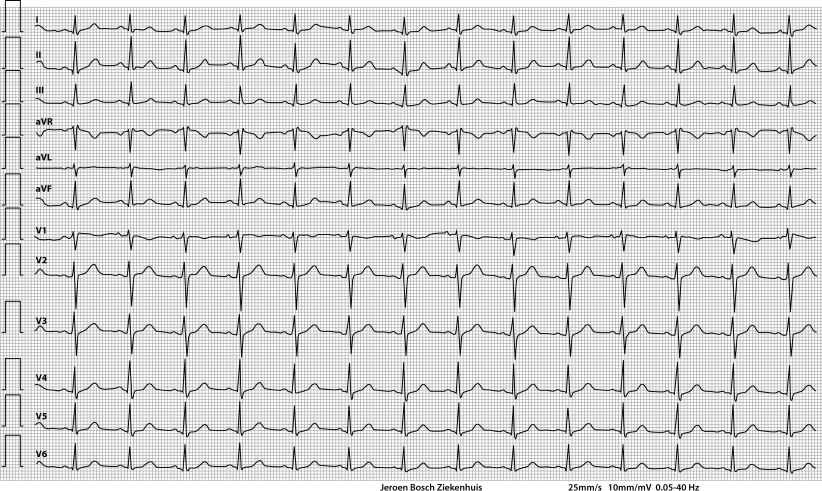

ECG on admission

In individuals with a normal baseline ECG, this pattern can be provoked by controlled infusion of sodium channel blocking agents for the diagnosis of Brugada syndrome [1]. However, intoxication with a sodium channel blocking agent may give rise to a transient Brugada-like pattern without an underlying Brugada syndrome.

In patients with a psychiatric history, one should consider involvement of a tricyclic antidepressant (TCA), since TCAs are known to result in sodium channel blockade [2]. Our patient turned out to be using nortriptyline, a TCA, amongst other non-tricyclic antidepressants. Therefore, the suspicion of an intoxication with this drug was raised [3]. Indeed, blood tests showed toxic levels of nortriptyline (507 µg/l (therapeutic levels: 50–150 µg/l; toxic levels: >500 µg/l), E‑10-OH-nortriptyline 386 µg/l).

Type 1 Brugada-like ECG pattern provoked by TCA intoxication.